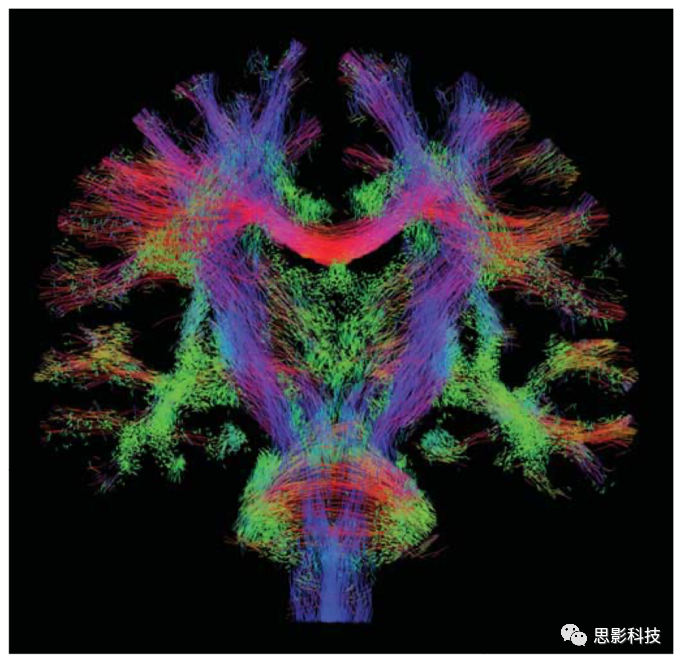

1.確定性纖維追蹤

確定性纖維追蹤主要使用FACT、steamline等追蹤方法根據(jù)張量主方向以及預(yù)設(shè)的偏轉(zhuǎn)角閾值、FA閾值等參數(shù)對(duì)全腦纖維束進(jìn)行構(gòu)建,而后通過(guò)設(shè)定ROI的方式追蹤特定纖維束,并計(jì)算纖維束的數(shù)目、平均FA等相關(guān)指標(biāo)。

圖例:全腦纖維束構(gòu)建